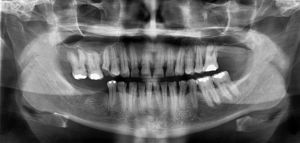

Caso clínicoPaciente do gênero masculino, 41 anos de idade, foi encaminhado ao nosso serviço para remoção de um implante dentário no interior do seio maxilar esquerdo. O paciente relatou que foi realizada a exodontia do elemento 26 (fig. 1), pois o mesmo apresentava-se condenado, tendo-se realizado a colocação imediata de um implante no alvéolo.

Após 5 semanas da colocação do implante, ao se alimentar, sentiu durante a mastigação um desconforto na área onde o implante havia sido colocado, mas não observou nada de anormal no local. Entretanto, procurou seu médico dentista tendo este solicitado uma radiografia panorâmica na qual se constatou a presença do implante no seio maxilar (fig. 2). Existiu, por parte do profissional, uma tentativa de remoção cirúrgica pelo local de inserção do implante através de sucção, mas sem êxito.

Ao exame complementar imagiológico, através da radiografia panorâmica (RP) (fig. 2), observou-se um corpo estranho compatível com implante dentário deslocado para o interior do seio maxilar esquerdo apresentando ausência de imagem radiopaca na área. Enquanto que a tomografia computadorizada de feixe cônico (TCFC) (fig. 4) revelou que no seio maxilar esquerdo existiam 2 pseudoquistos antrais, sendo o primeiro localizado na parede anterior e o segundo na parede posterior do soalho, unidos por espessamento mucoso envolvendo o implante dentário.